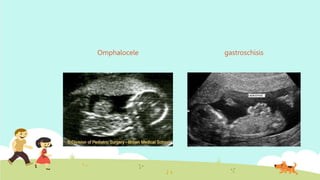

Omphalocele Gastroschisis